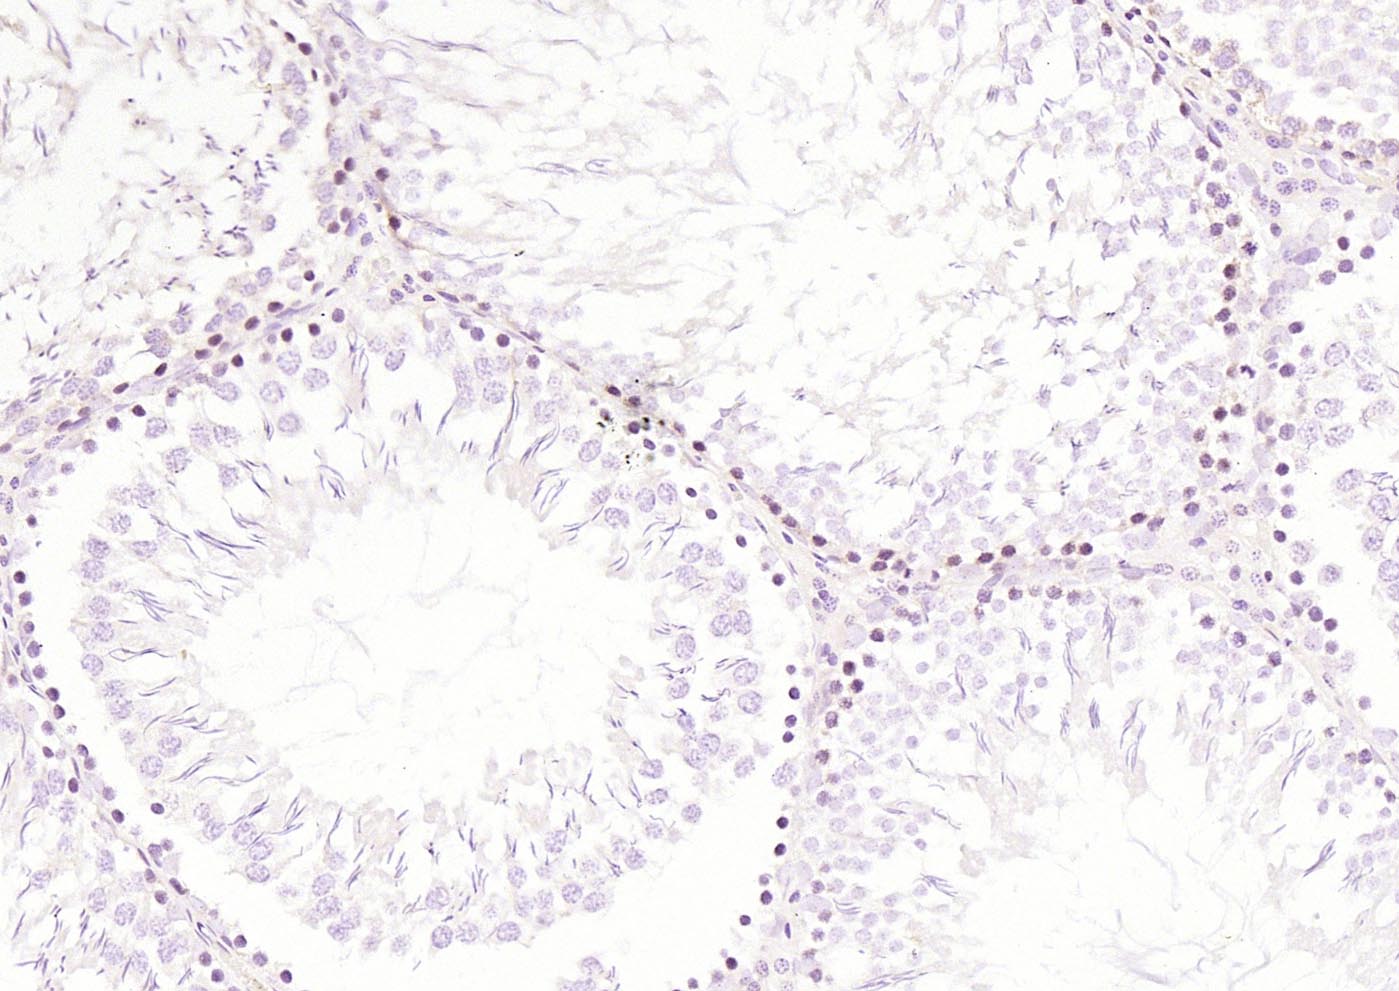

Paraformaldehyde-fixed, paraffin embedded (mouse skin); Antigen retrieval by boiling in sodium citrate buffer (pH6.0) for 15min; Block endogenous peroxidase by 3% hydrogen peroxide for 20 minutes; Blocking buffer (normal goat serum) at 37°C for 30min; Incubation with (RelB) Polyclonal Antibody, Unconjugated (bs-3562R) at 1:200 overnight at 4°C, followed by operating according to SP Kit(Rabbit) (sp-0023) instructionsand DAB staining.